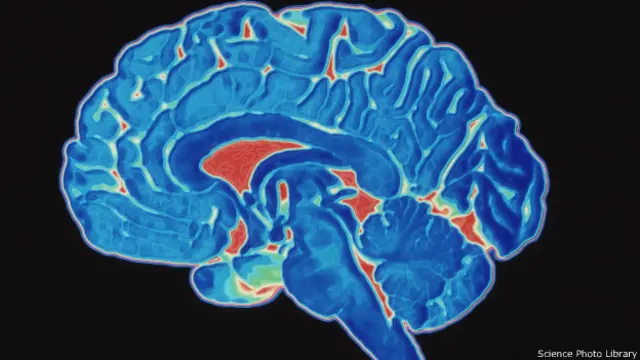

Автор фото, Science Photo Library